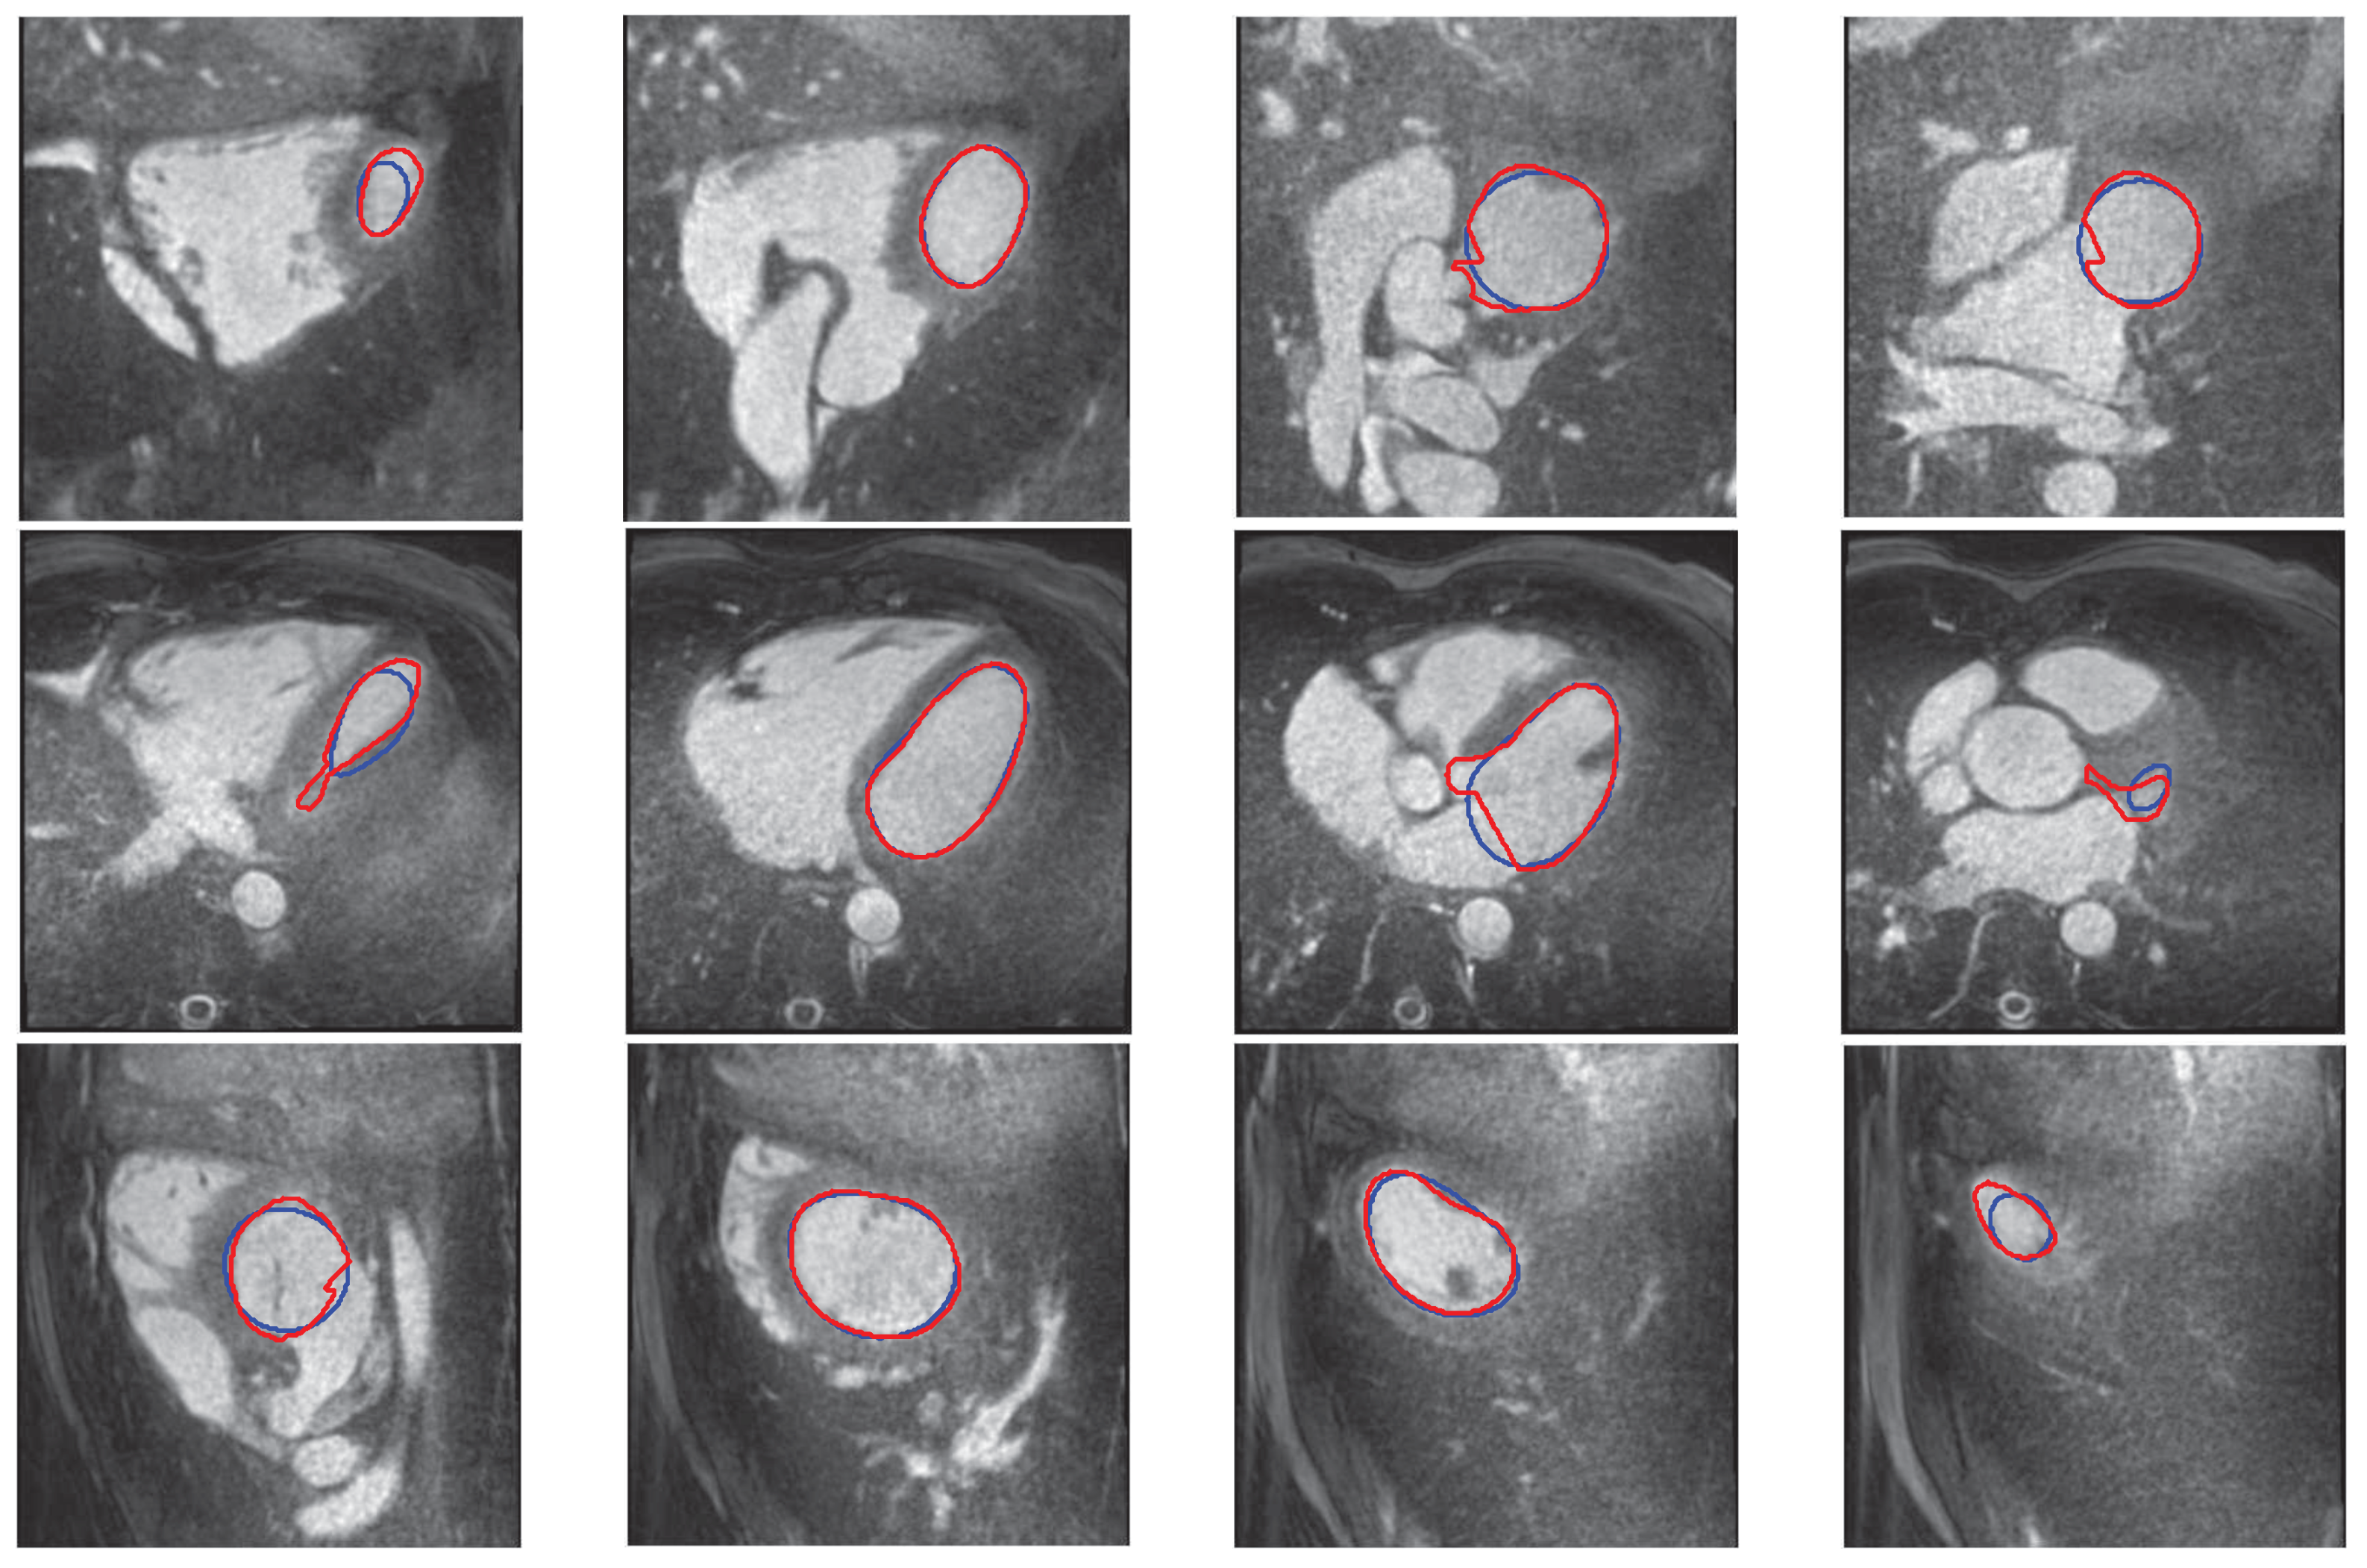

3.2. 3D Interpolation Evaluation

4. Discussion